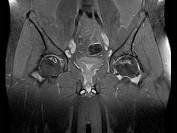

问题 男,47岁,长期左髋痛,请结合CR和MRI片,选择最可能的诊断 ( )

选项 A、暂时性骨质疏松 B、股骨头缺血坏死 C、退变性囊肿 D、骨岛 E、髋关节结核

答案 B